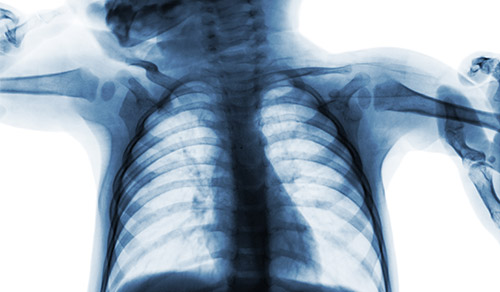

Pediatric pulmonologists from Columbia and Weill Cornell Medicine provide specialized testing and novel therapies for respiratory disorders in children of all ages. Through major centers in cystic fibrosis, asthma, sleep disorders, and aerodigestive and neuromuscular disorders, physicians at the Children's Hospital of New York partner with the patient and their parents to personalize treatment, including participation in clinical trials of the latest therapies, with the goal of helping young patients lead a normal and healthy childhood.

Pediatric Pulmonology